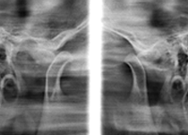

Radiografia das Articulações Temporomandibulares

Utilizada para avaliar os contornos ósseos das cavidades articulares e dos côndilos (cabeças da mandíbula), bem como seus posicionamentos. O exame pode ser obtido em oclusão dentária, repouso e máxima abertura bucal, conforme a necessidade do caso.